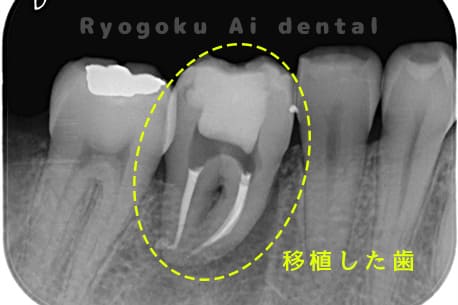

他院で右下の根の治療を行い、セラミックを被せる説明をされていたが、根の治療が終わらないため転院された患者さんです。隣の親知らずの抜歯の必要性と、根の治療を行なっている歯牙の予後が悪いため、移植治療を提案し、右下の親知らずの抜歯と同時に、右下の奥歯(7番)への移植治療を行いました。被せ物を行う必要もなく、順調に経過してます。